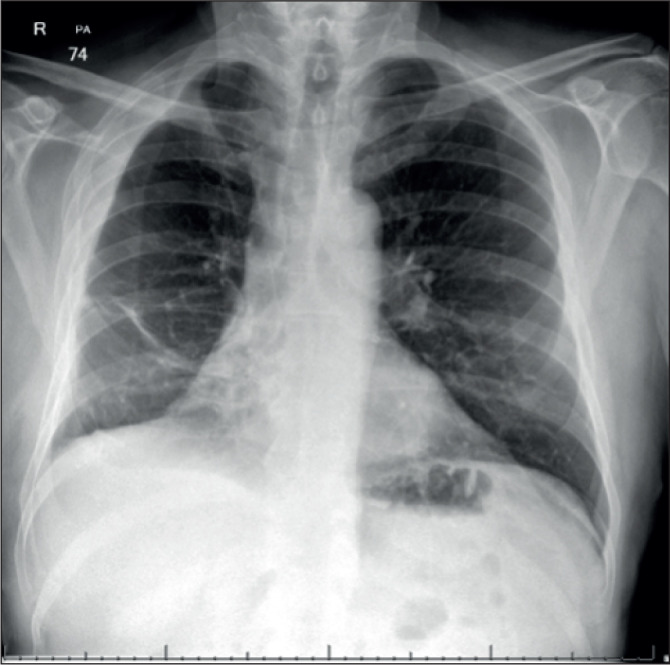

Extrapleural Haematoma following Percutaneous Coronary Intervention.

Abstract Image